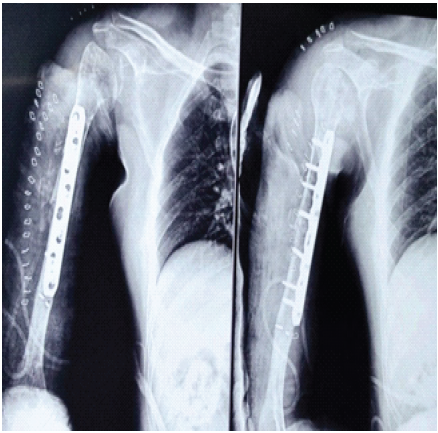

The post-operative course was uneventful. Early shoulder and elbow mobilization was initiated following wound healing. Immediate post-operative radiographs demonstrated stabilization of the right mid-shaft non-union with plate osteosynthesis, adequately bridging the previous fracture site and maintaining satisfactory alignment and length of the humerus (Fig. 5).

Figure 5: Immediate post-operative anteroposterior and lateral radiographs showing stabilization of the right mid-shaft nonunion with plate osteosynthesis, bridging the previous fracture site and maintaining satisfactory alignment and humeral length.

At the 6th post-operative month follow-up, the patient reported complete resolution of pain and significant functional improvement, achieving a near-full range of motion and return to daily activities. Radiographs of the right humerus at the 6th post-operative month showed satisfactory fracture union with bony callus formation at the fracture site, with no evidence of implant breakage or loosening (Fig. 6).

Figure 6: Anteroposterior and lateral radiographs of the right humerus at the 6th post-operative month demonstrating satisfactory fracture union with bony callus formation and no evidence of implant loosening or breakage.